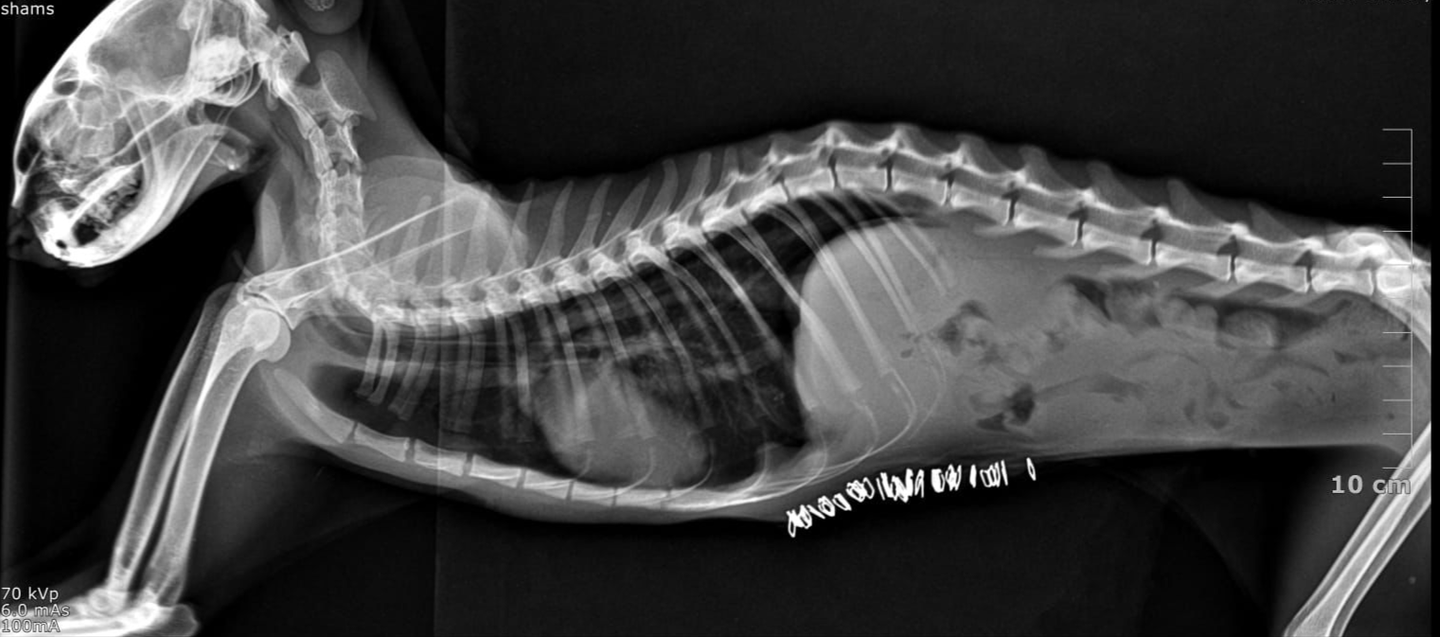

. Thoracic Radiographs

• Loss of normal diaphragmatic line

• Loops of gas-filled bowel visible within the thoracic cavity

• Heart silhouette displaced cranially

• Reduced lung fields (atelectasis)

Loss of normal diaphragmatic line Loops of gas-filled bowel visible within the thoracic cavity